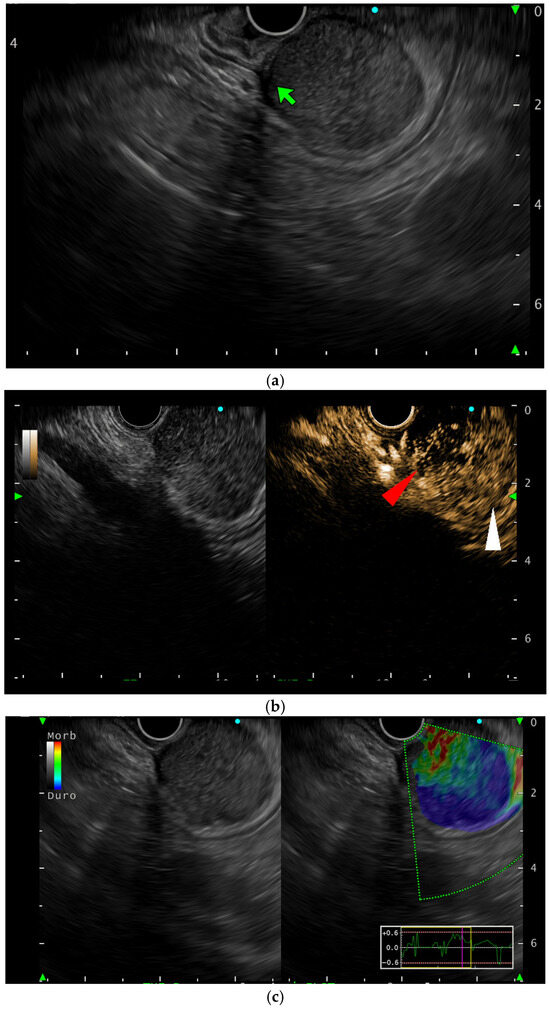

EUS was performed to evaluate the origin of the lesion, which arose from the muscular layer (4th) of the gastric wall (Figure 2a). Moreover, the lesion appeared hypoechoic and heterogeneous, with regular borders. It exhibited a heterogeneous contrast enhancement pattern after injection of ultrasonographic contrast dye (SonoVue): a hypoenhancing region (area A) and a hyperenhancing region (area B) (Figure 2b).

Figure 2.

EUS view of the lesion: (a) B-mode showing the lesion originating from the 4th layer (green arrow); (b) contrast-enhanced view showing the two different areas (area A: red arrow; area B: white arrow); (c) elastography showing the two different areas: area B is blue (stiff) while area A is green (soft).

E-EUS confirmed different stiffness between the two areas; elastography and contrast-enhanced EUS revealed two distinct regions: a firm, hyperenhancing area (B) and a softer, hypoenhancing area (A) (Figure 2c). FNB was performed, targeting both the areas through the use of a Franseen-tip needle (22 gauge) with the guidance of CE-EUS and E-EUS, introducing the needle once for each targeted area, and samples were sent separately for histological evaluation. Both samples were of high-quality according to the pathologist evaluation, showing an immunohistochemistry positive for DOG1, CD34, and CD117, and the final diagnosis was consistent with a mixed-type gastrointestinal stromal tumor (GIST) according to WHO 2019 classification. However, the Ki-67 labeling index exceeded 6% (Figure 3a), a value that some studies associate with higher recurrence risk, suggesting a potentially underestimated malignant potential. More specifically, the histology of area A revealed a spindle cell neoplasm with interlacing fascicles and focal epithelioid features, as well as a single necrotic area (Figure 3b). On the other hand, area B showed a similar neoplastic proliferation, again with mixed spindle and epithelioid morphology, but with more extensive necrotic areas (Figure 3c). Therefore, the marked difference in enhancement and stiffness between area A (hypoenhancing, soft) and area B (hyperenhancing, stiff) corresponded histologically to areas with differing degrees of necrosis and regressive changes (Figure 3d,e). The patient was sent to the abdominal surgeons to undergo gastric resection.